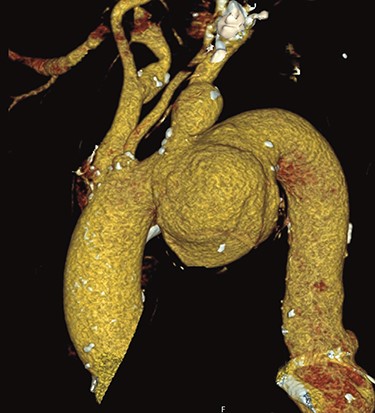

A 66-year-old patient suffering from a degenerative aortic aneurysm involving the ascending aorta, the arch and the thoracoabdominal aorta was scheduled for ascending aortic and extended aortic arch replacement with a frozen elephant trunk (fET) in preparation for a second-stage thoracic endovascular aortic repair. The preoperative computed tomography scan revealed a maximum diameter of 7 cm of a berry-like sack connected to the transverse arch (Fig. 1). On echocardiography, the aortic valve was competent.

Preoperative CT reconstruction of the ascending and arch aneurysm.